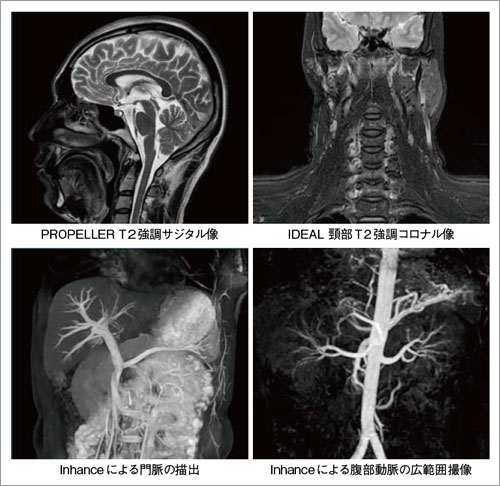

PROPELLER,MERGE,LAVA,VIBRANT,Inhanceなど,従来から製品化されているアプリケーションをこの新しいハードウェアに最適化させることで進化させつつ,研究機関向けのハイエンド装置であるDiscovery MR750や3T/1.5T MR「Signa HDxt」に採用されているIDEAL,Cube,SWAN,COSMICなどの最先端アプリケーションを搭載し,高いパフォーマンスを実現している(図6)。特に,従来より搭載要望の高い非造影MRAアプリケーションであるInhanceは,撮像機能をさらに充実させた。